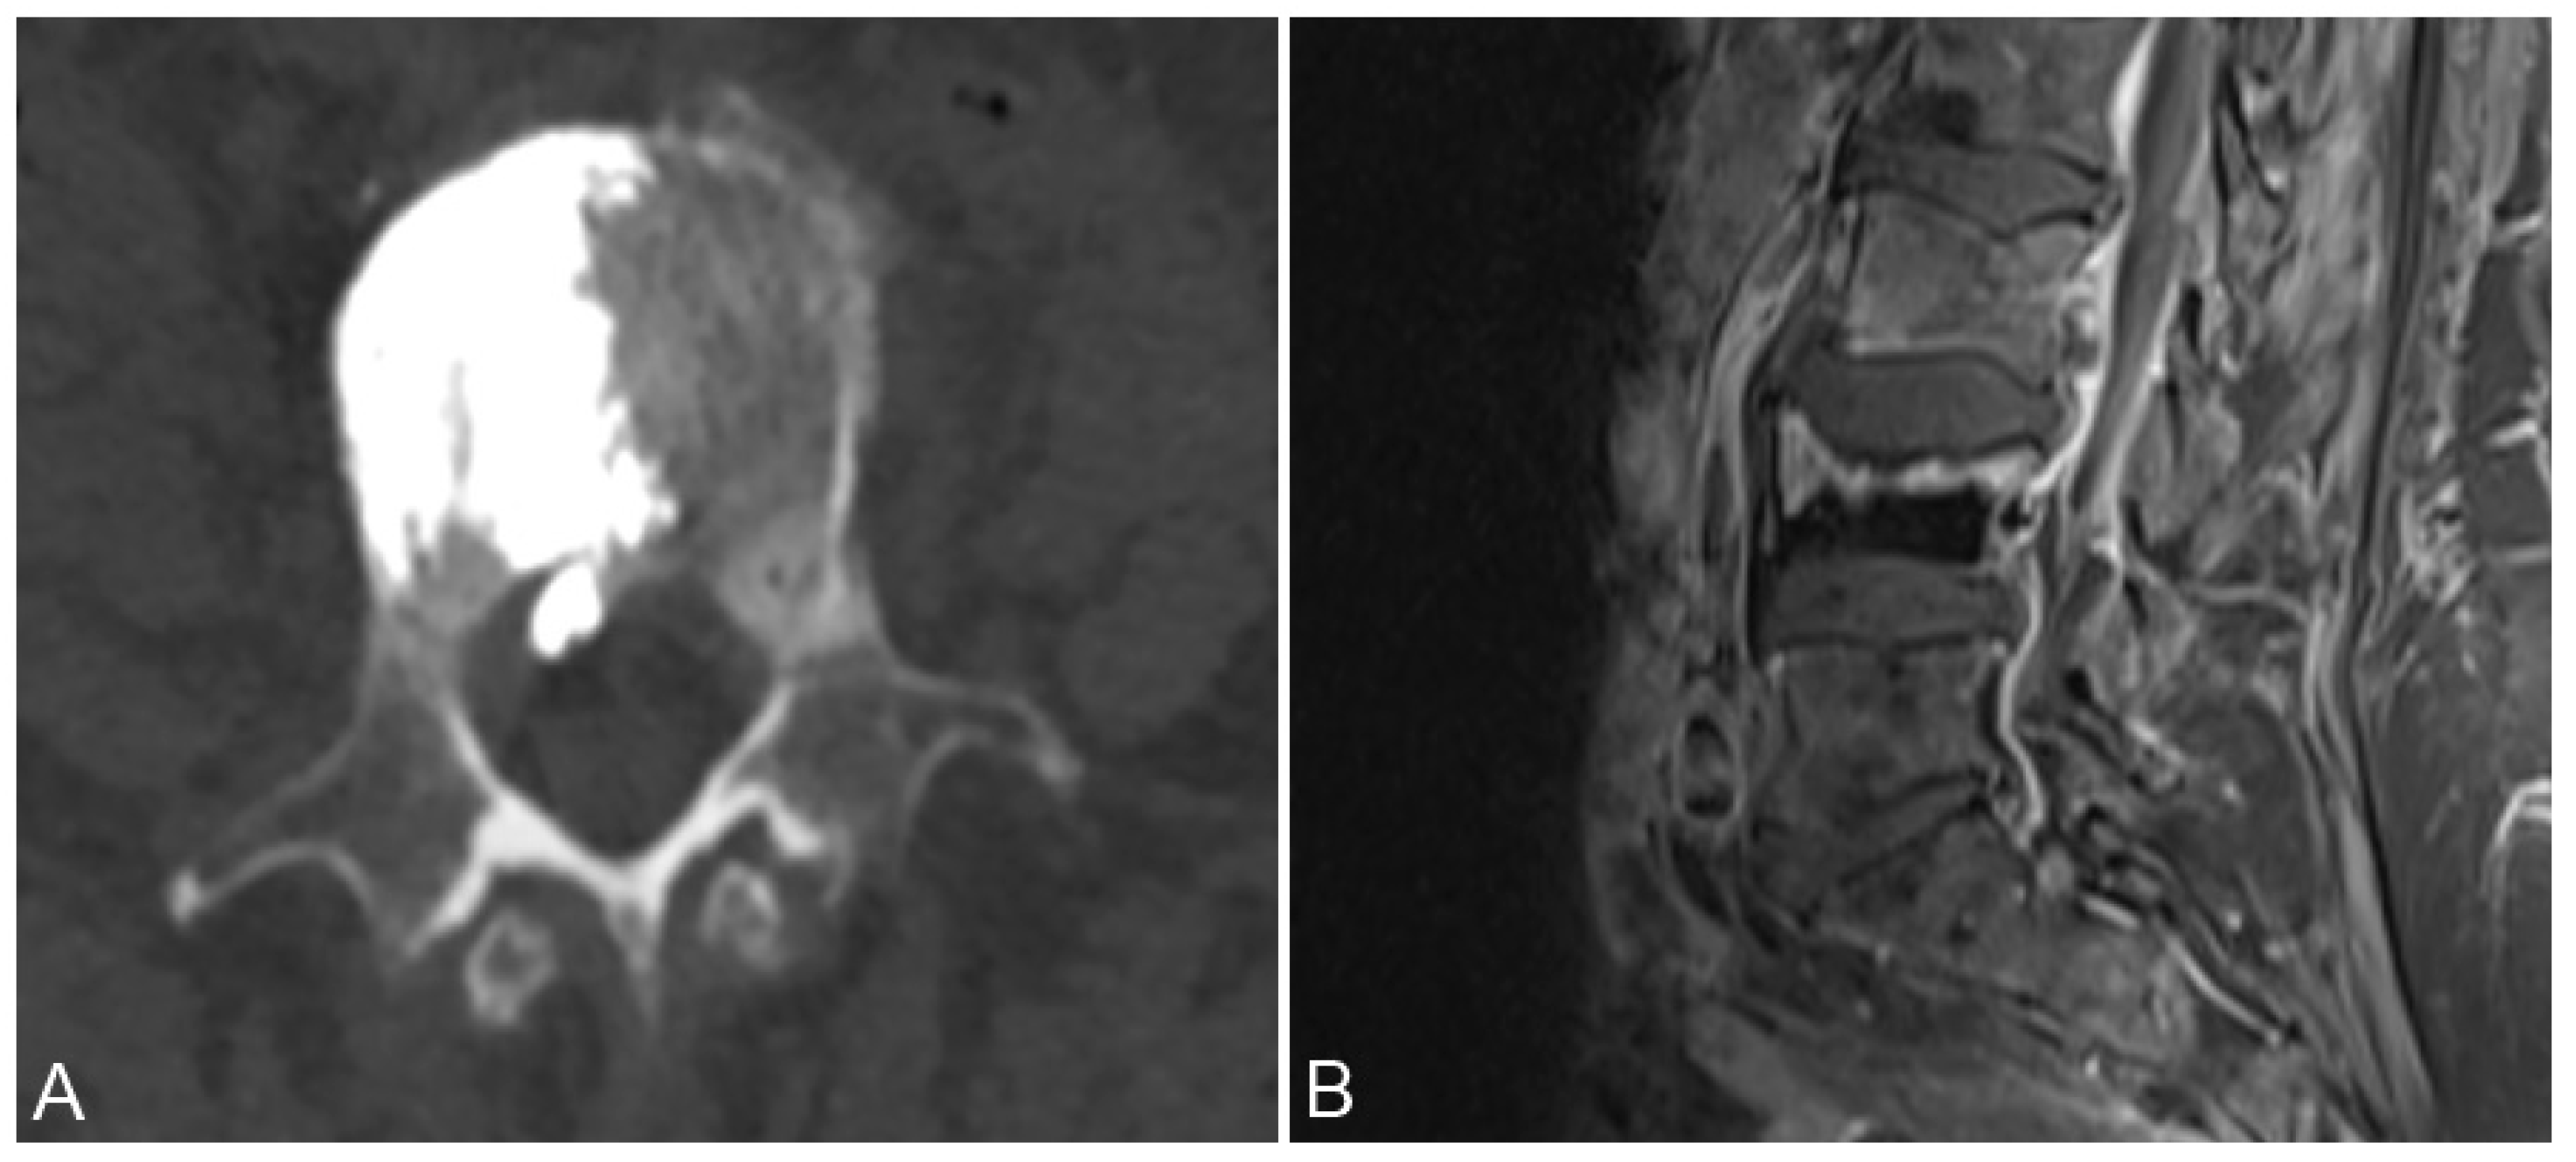

3.1. Epidural and Foraminal Cement Leakage